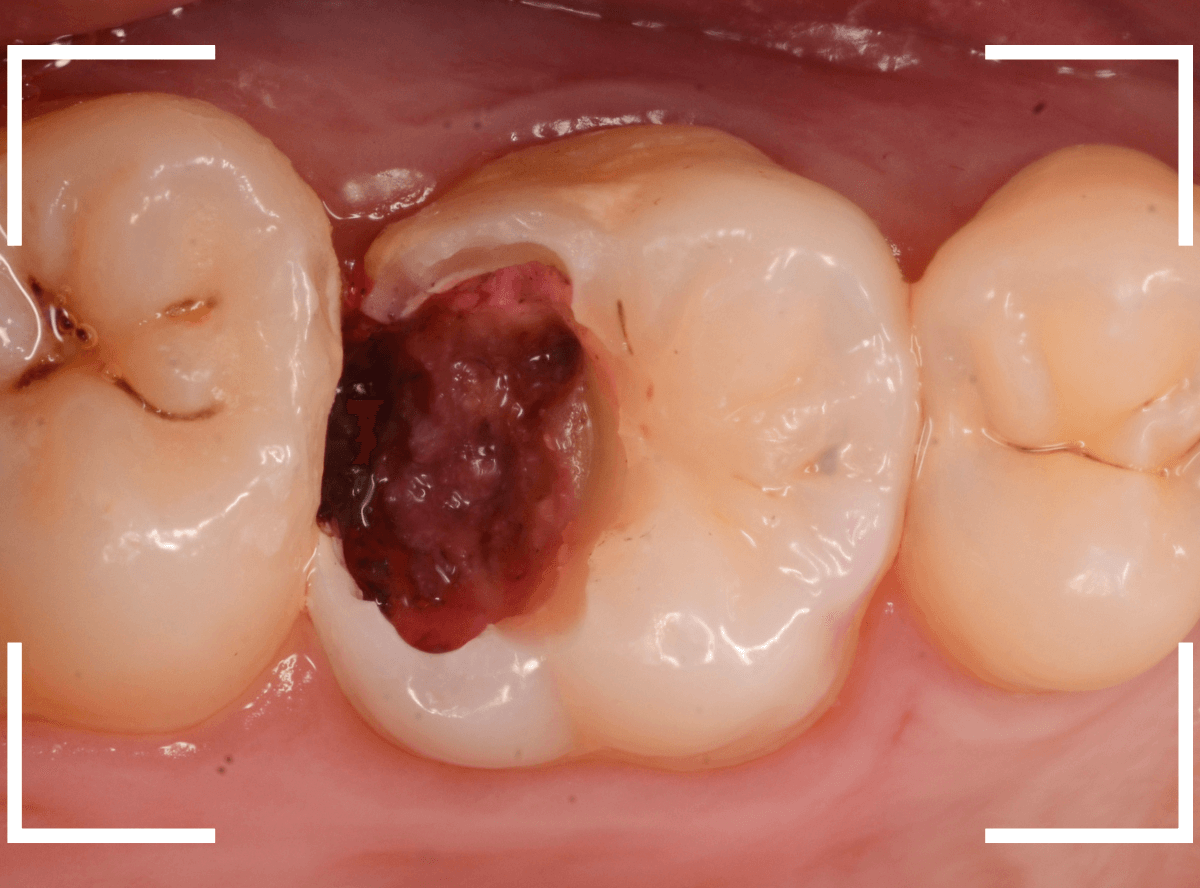

止血しながら、電気メスで歯の中に入り込んだ歯肉を除去します。

虫歯と入り込んだ歯肉でぐちゃぐちゃになっている状態でした。

これでは、痛みが出てもおかしくありません。

慎重に全ての虫歯を除去したところです。

〇部が神経の入り口が見えているところです。

神経を保護する処置をして、しばらく経過観察しますが、痛みが出て神経を除去する必要が出る可能性も高いです。

痛みが出ませんように・・・。